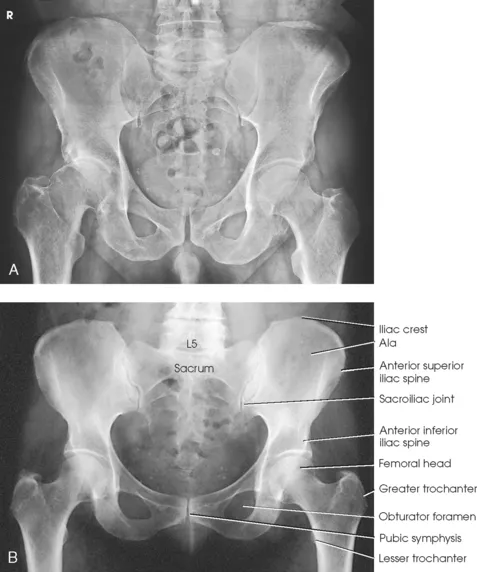

- Composition: A basin-like ring formed by two innominate bones, the sacrum, and the coccyx.

- Each innominate bone comprises the ilium, ischium, and pubis, which fuse at the acetabulum.

- Key Articulations:

- Sacroiliac (SI) Joints: Link the axial skeleton (sacrum) to the iliac bones.

- Pubic Symphysis: A cartilaginous joint that unites the pubic bones anteriorly.